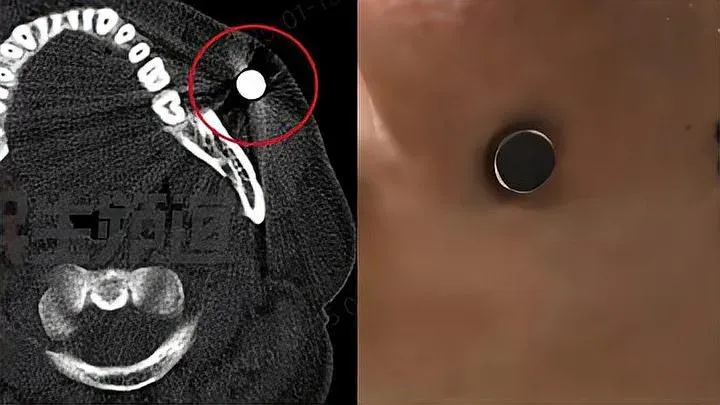

幼童